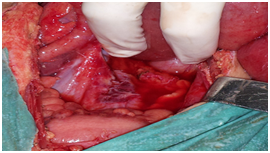

All the patients were explored urgently by midline incisions. The different types of hernia found were through: Paranormal orifice: 3 left paraduodenal (Figures 2) (Figure 3A) (Figure 3B), 2 right paraduodenal, 1 intra-mesosigmoidal and 1 retrocecal. Abnormal pathologic orifice: 2 trans-mesenteric (Figures 4A-4C), 1 in the posterior cavity through a colo-omental dissinsertion hole Figure 5 and 1 trans-omental. The Reduction of the herniated viscera was never a problem but a bowel necrosis was found in two cases, which required dilatation of the hernial orifice and resection of 1, 25m and 60cm of small bowel with immediate restoration of continuity. The closure of peritoneal fossae or an abnormal orifice was done easily with a resorbable suture (Table 2). We had no death in our patients. Two cases of wound infection were reported classified Grade I in the Clavien-Dindo classification of surgical complications. These patients were treated by antibiotics and had local treatment. The length of hospital stay was 8 days (3-11days). In the follow-up, there was no recurrence.

Figure 5 The orifice of a tran’s mesocolic hernia.